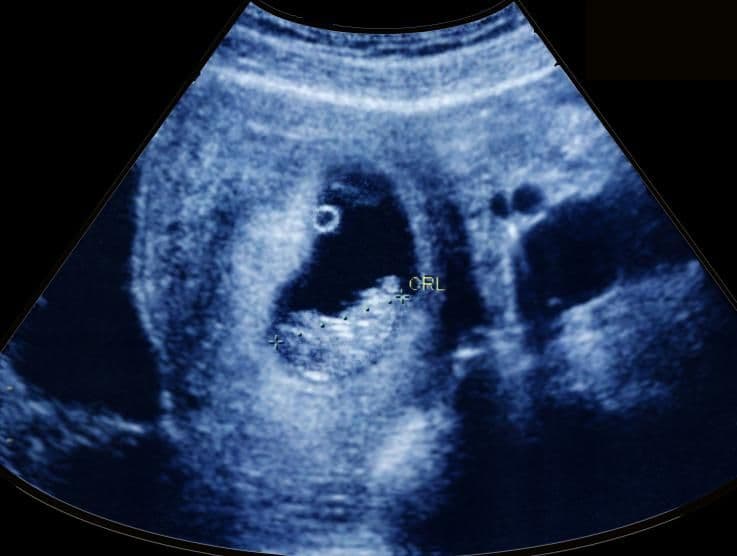

This image shows the yolk sac at the 12 o’clock position with the placenta seen as a thickening to the lining of the uterus on the left. The baby is in the lower part of the uterus and is positioned lying on her back.

At your ultrasound scan, the pregnancy is dated according to your baby’s length from crown (head) to rump (bottom) because she is – and will remain – quite curled up. This is known as the CRL (crown–rump length).

As your baby can flex her spine and stretch her neck, this measurement needs to be taken with your baby in a specific position so it can take some time to achieve. The measurement is used to estimate your baby’s date of delivery and this may be different to the EDD you calculated.

On this first ultrasound scan it should be possible to recognize all four limbs, the hands and feet, the spine, some aspects of brain development, the fluid-filled stomach, and the bladder. From now on your baby’s kidneys will be producing small amounts of very dilute urine and the bladder will start to fill.